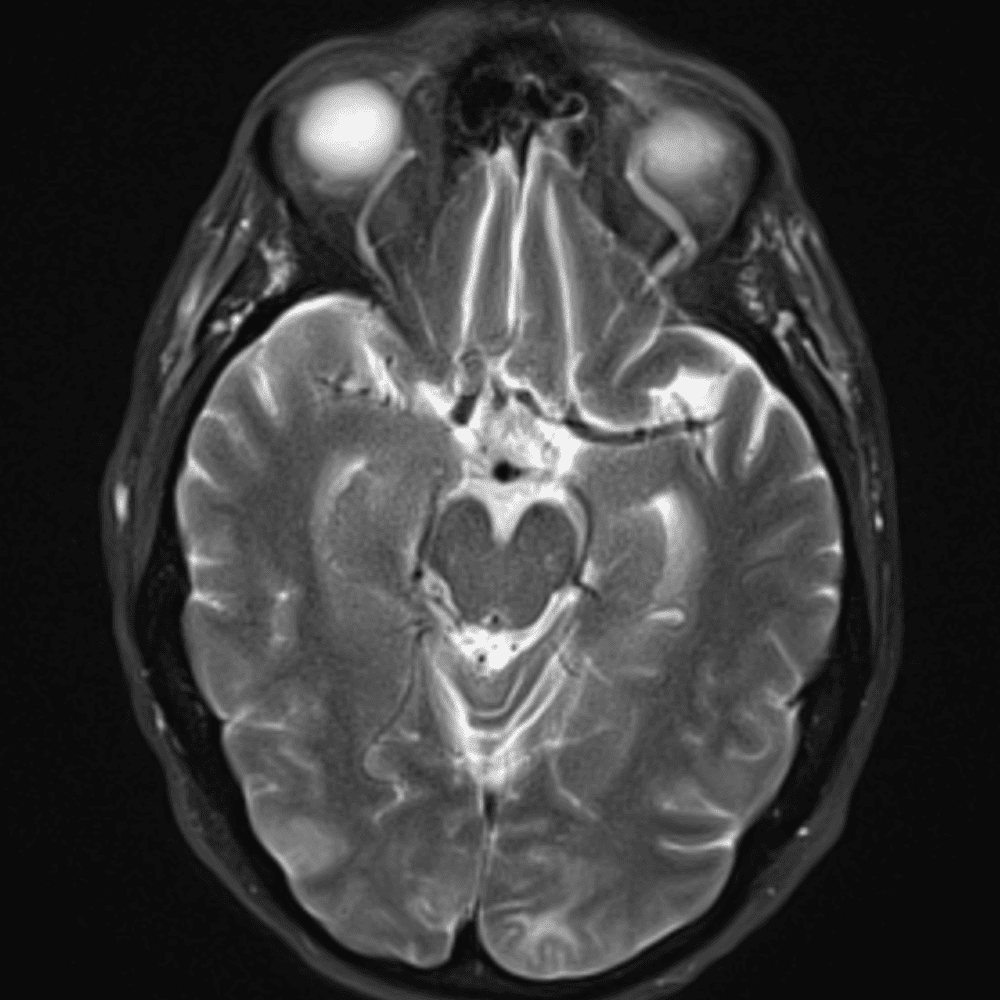

๋‹น์ง ์‹œ ํ”ํžˆ ๋ณผ ์ˆ˜ ์žˆ๋Š” ์‚ฌ๋ก€์˜ ์ „ํ˜•์ ์ธ ์˜ˆ๋ฅผ ํฌํ•จํ•ฉ๋‹ˆ๋‹ค.

39 ์‚ฌ๋ก€

์—ฐ์Šต

๋ฏธ๋ฌ˜ํ•˜๊ฑฐ๋‚˜ ์–ด๋ ค์šด ์‚ฌ๋ก€์™€ ์ผ๋ถ€ ์ •์ƒ ์‚ฌ๋ก€๋ฅผ ํฌํ•จํ•˜์—ฌ ๋‹น์ง์„ ์‹œ๋ฎฌ๋ ˆ์ด์…˜ํ•ฉ๋‹ˆ๋‹ค.

50 ์‚ฌ๋ก€